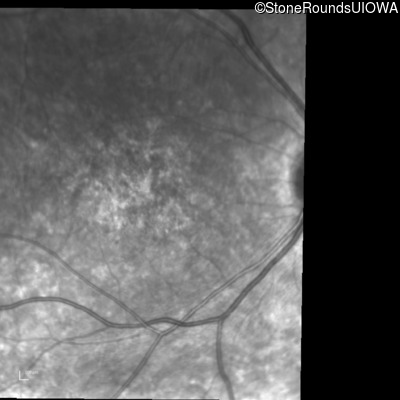

Infrared Fundus Photograph - Right - 10/160 sc

Exemplar